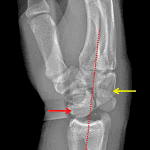

- Acute comminuted scaphoid waist fracture with midcarpal dislocation

- Overlying soft tissue swelling

Acute comminuted scaphoid waist fracture with midcarpal dislocation. Overlying soft tissue swelling.